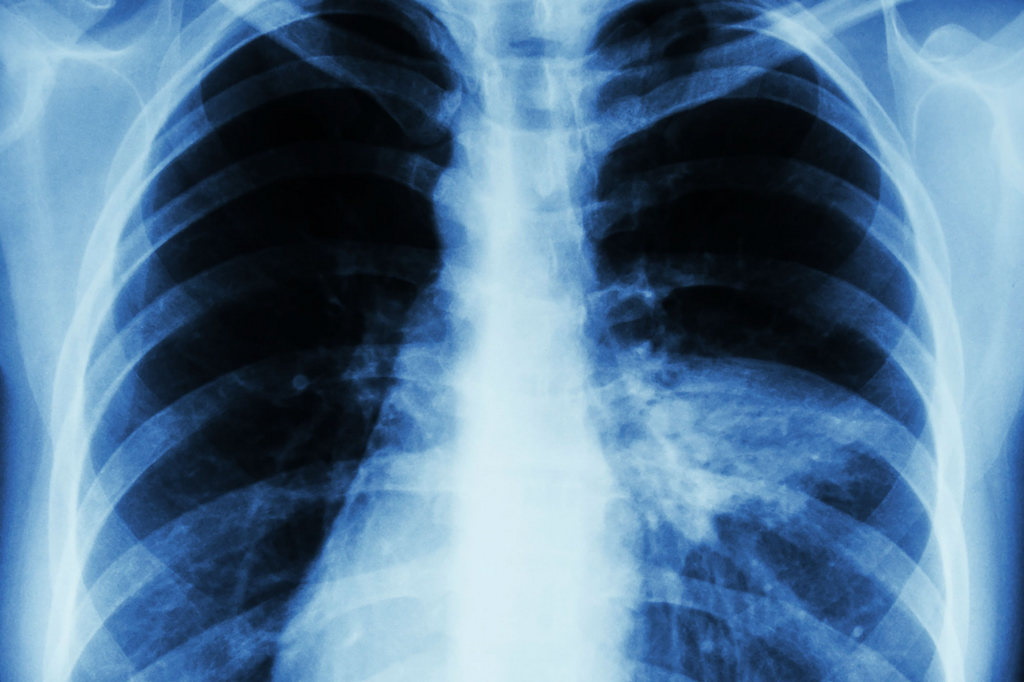

Алматы қалалық клиникалық ауруханасының пульмонолог дәрігері Ақжарқын Қалдыбек пневмонияның белгісіз белгілері туралы айтты.

Оның айтуынша, пневмония кейде басқа аурулардың белгілерімен жасырын түрде өтуі мүмкін. Әдеттегі пневмония жөтелмен, қақырық шығарумен, жоғары температурамен және әлсіздікпен басталады. Бірақ атиптік пневмония қызу көтерілмей, бас және бұлшықет ауырсынуларымен, құрғақ жөтелмен немесе тамақтың ауруымен көрінуі мүмкін. Сондай-ақ кеуде қуысының невралгияға ұқсас ауырсынуы да белгісіз белгі болып табылады.

Пневмонияның бактериялық, вирустық және саңырауқұлақтық түрлері бар. Қазіргі уақытта көбінесе бактериялық пневмония кездеседі. Атиптік пневмония қауіпті, өйткені ол антибиотиктерге жауап бермеуі мүмкін. Сондықтан қоздырғыштың түрін анықтау маңызды.

Дәрігер кейбір пневмония жағдайлары жаңа коронавирус штаммдарымен байланысты болуы мүмкін екенін айтты. Қазіргі пневмония қысқа инкубациялық кезеңімен ерекшеленеді — ауру 3-4 күн ішінде дамуы мүмкін және жылдам өтеді.

Егер суық тию белгілері байқалса, міндетті түрде дәрігерге қаралу қажет. Өзін-өзі емдеуге болмайды, өйткені пневмонияның ауырлығын және емдеу тәсілін тек маман анықтай алады. Уақтылы диагноз қойылып, ем басталса, бактериялық пневмония жақсы емделеді.